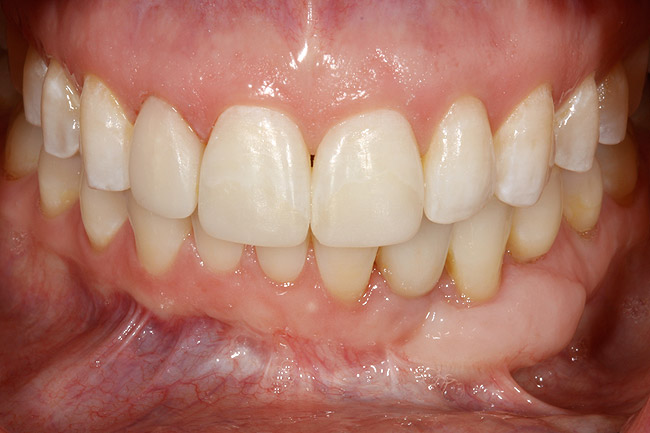

Figure 24  Definitive restoration of tooth No. 23.

Figure 24